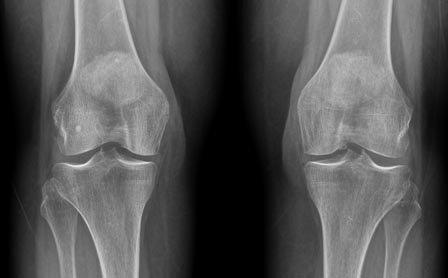

Los investigadores trabajaron en primer lugar en los grupos de células que se dividen rápidamente en los extremos de los huesos de ratón y posteriormente vieron que podrían formar todas las partes del hueso: hueso, cartílago y el estroma, el tejido esponjoso en el centro de los huesos que ayuda a las células madre hematopoyéticas a convertirse en sangre y en células inmunes.

A continuación identificaron un único tipo de célula que podría, por sí misma, formar todos estos elementos del esqueleto. No contentos con este hallazgo, los expertos fueron mucho más lejos, cartografiando el árbol evolutivo de las células madre del esqueleto para rastrear con precisión cómo se transforman en células progenitoras intermedias y, finalmente, en cada tipo de tejido esquelético. «Mapear el árbol nos permitió entender en profundidad todos los interruptores genéticos que tienen que activarse para dar lugar a los progenitores más específicos y a las células especializadas», afirma Charles Chan.Gracias a esta información, los investigadores fueron capaces de encontrar factores que, cuando se proporcionan en la cantidad correcta y en el momento adecuado, dirigen el desarrollo de las células madre esqueléticas en células óseas, cartilaginosas o el estroma. «Si esto se traduce en los seres humanos, entonces tendríamos una forma de aislar las células madre del esqueleto y rescatar el cartílago del desgaste o del envejecimiento, reparar huesos que tienen fracturas que no cicatrizan y renovar el nicho de la médula ósea en aquellas personas en las que está dañado», subraya Irving Weissman, director del Instituto Stanford para Biología de Células Madre y Medicina Regenerativa.